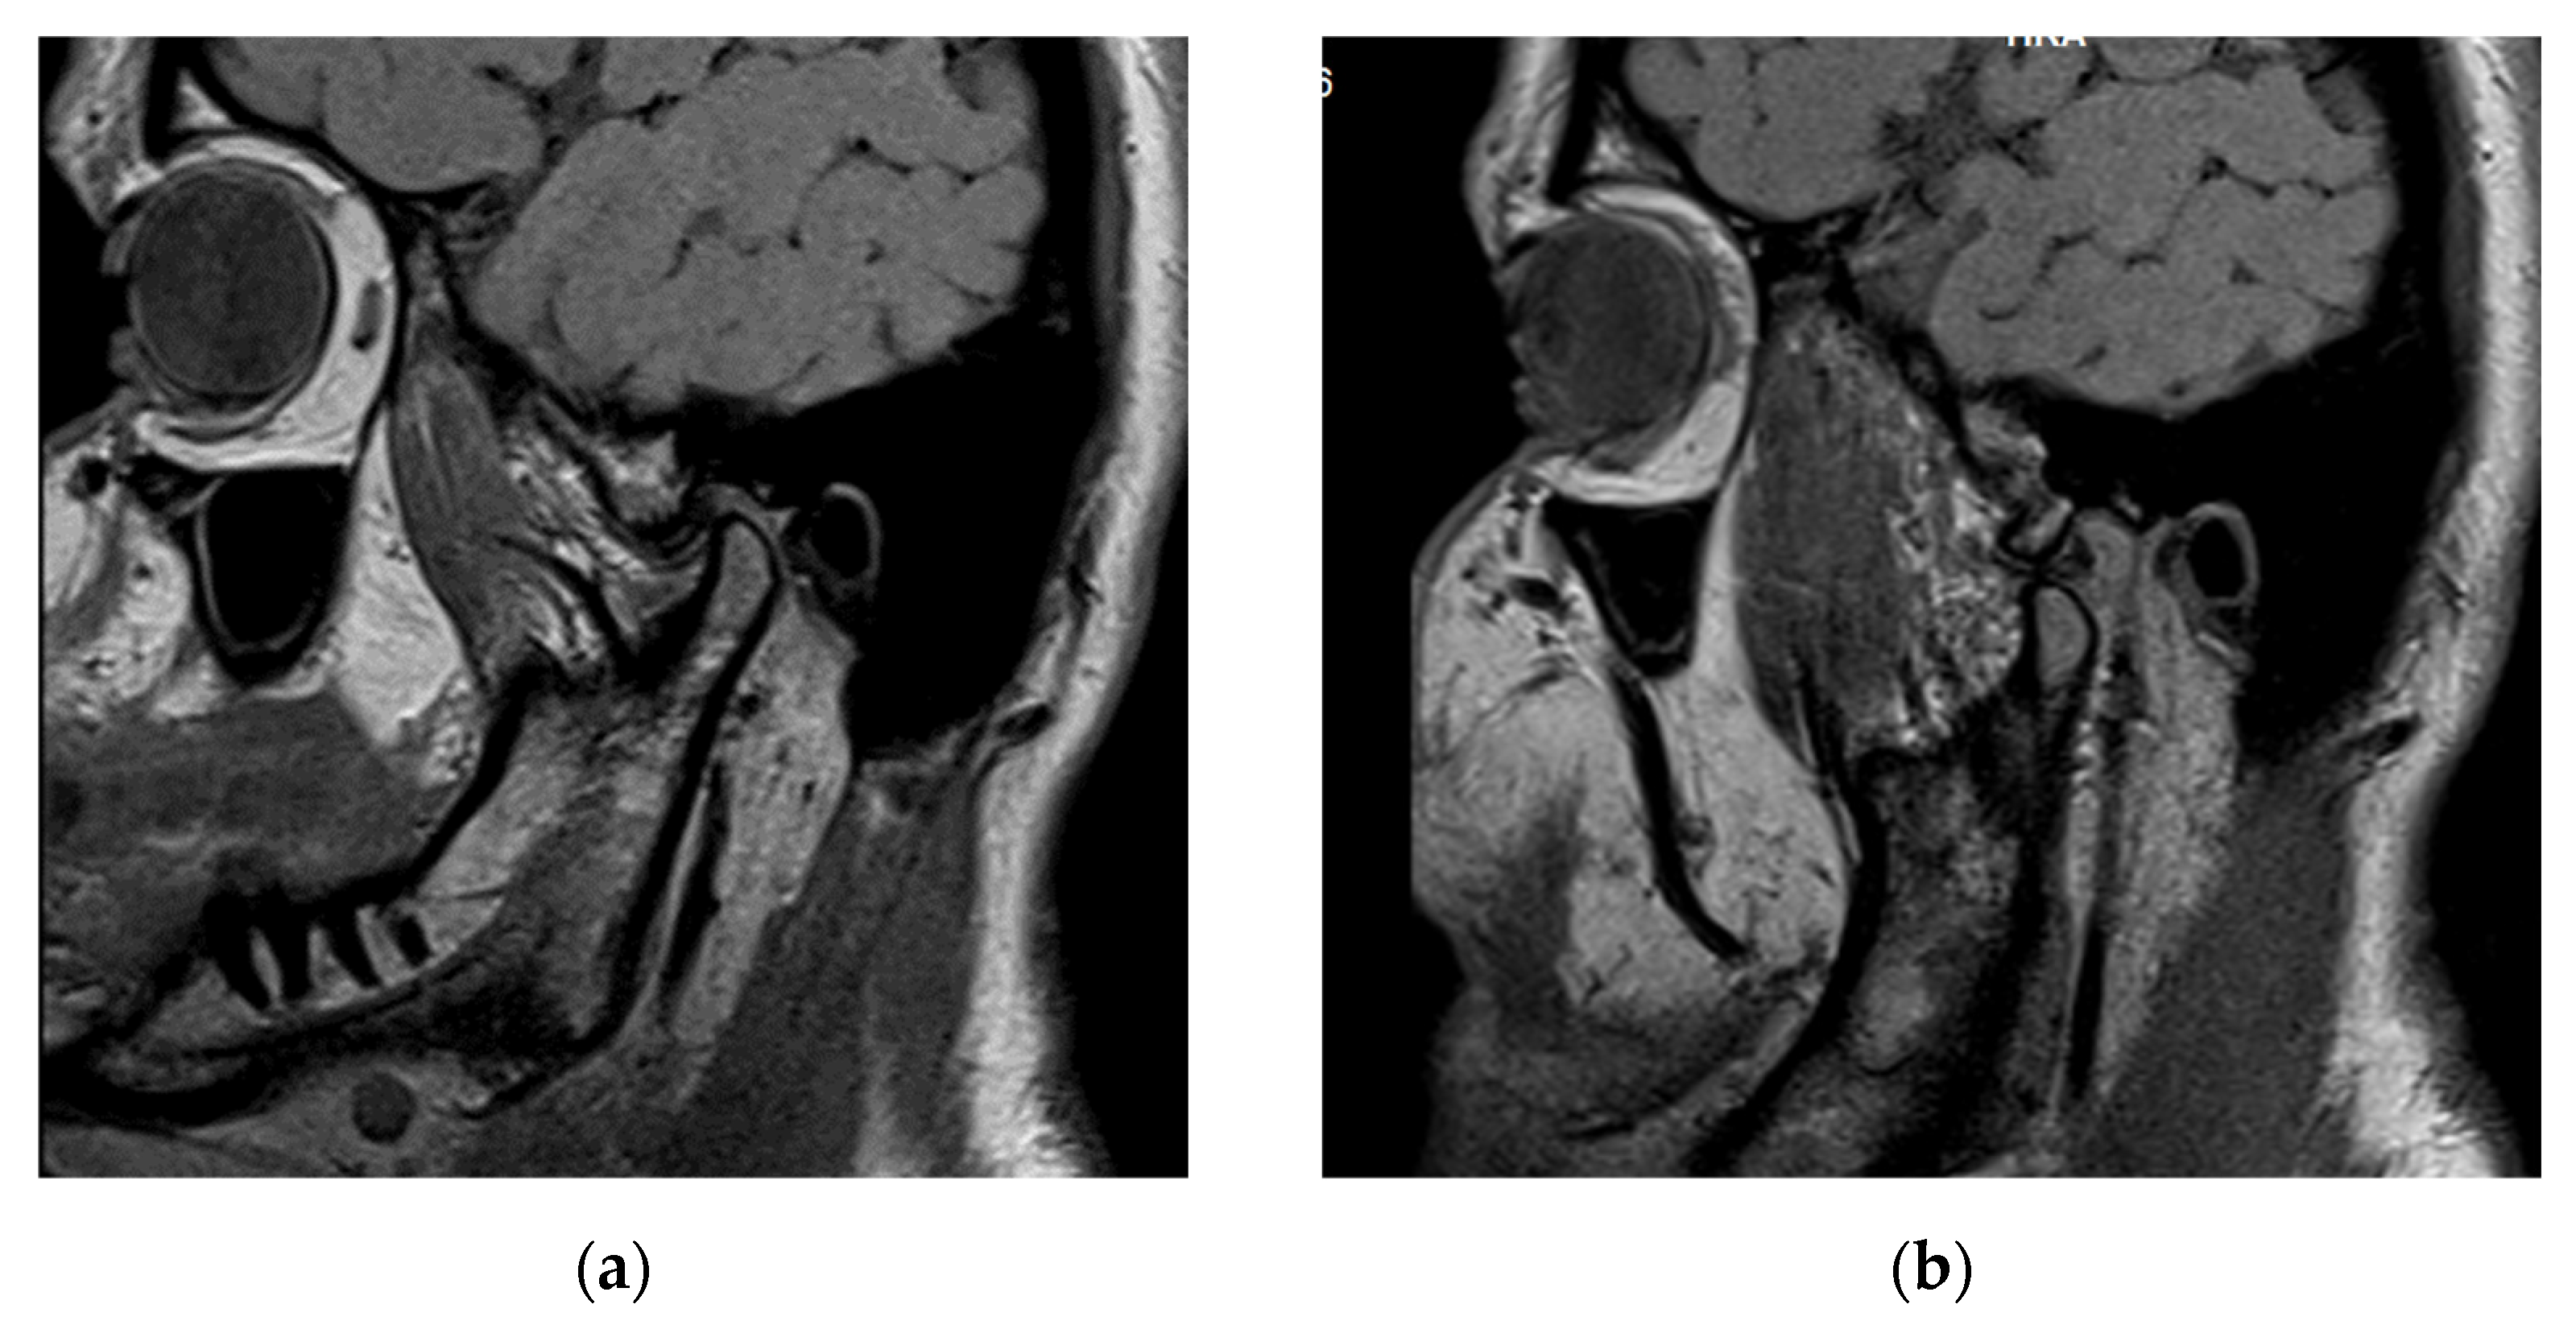

3.3. Case Report